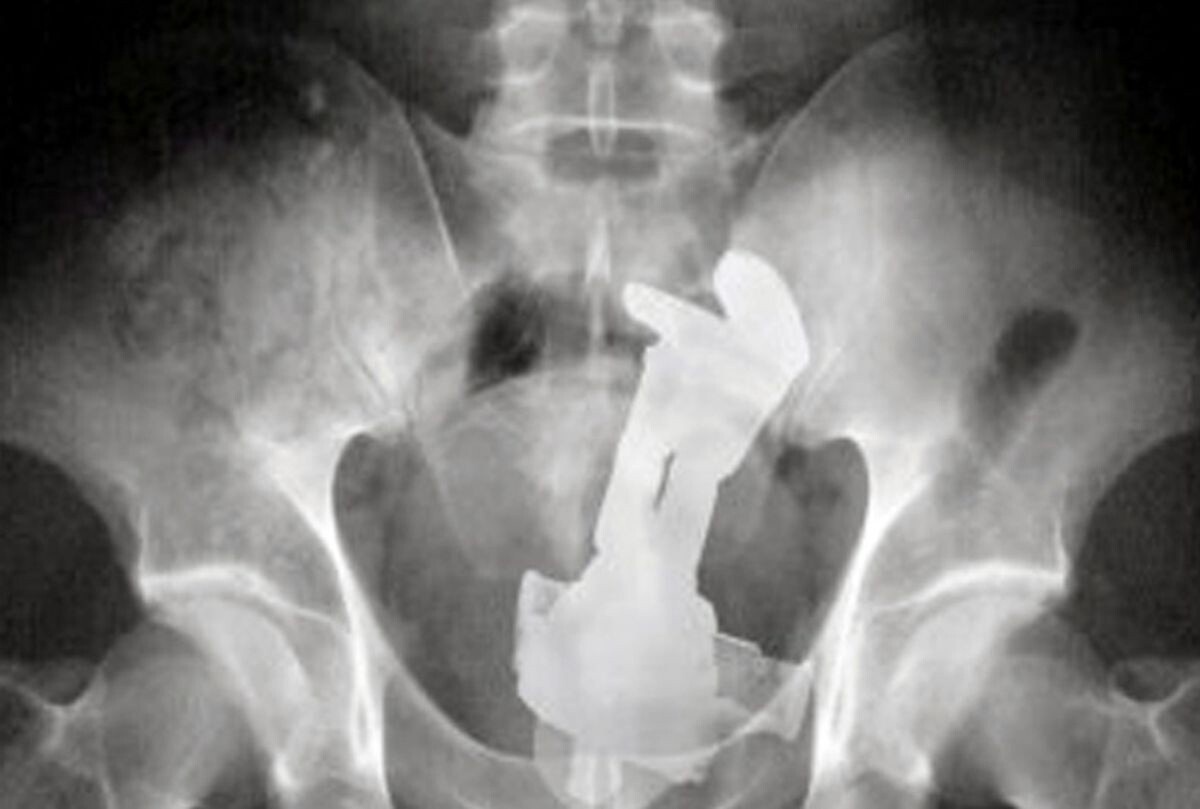

【画像】アメリカで起きた衝撃の事件、ホモの緊急搬送の真相wwwwwwwwwwwwwwwwwwwwwwwww

バズ・ライトイヤーなのですか?

バズゥ!